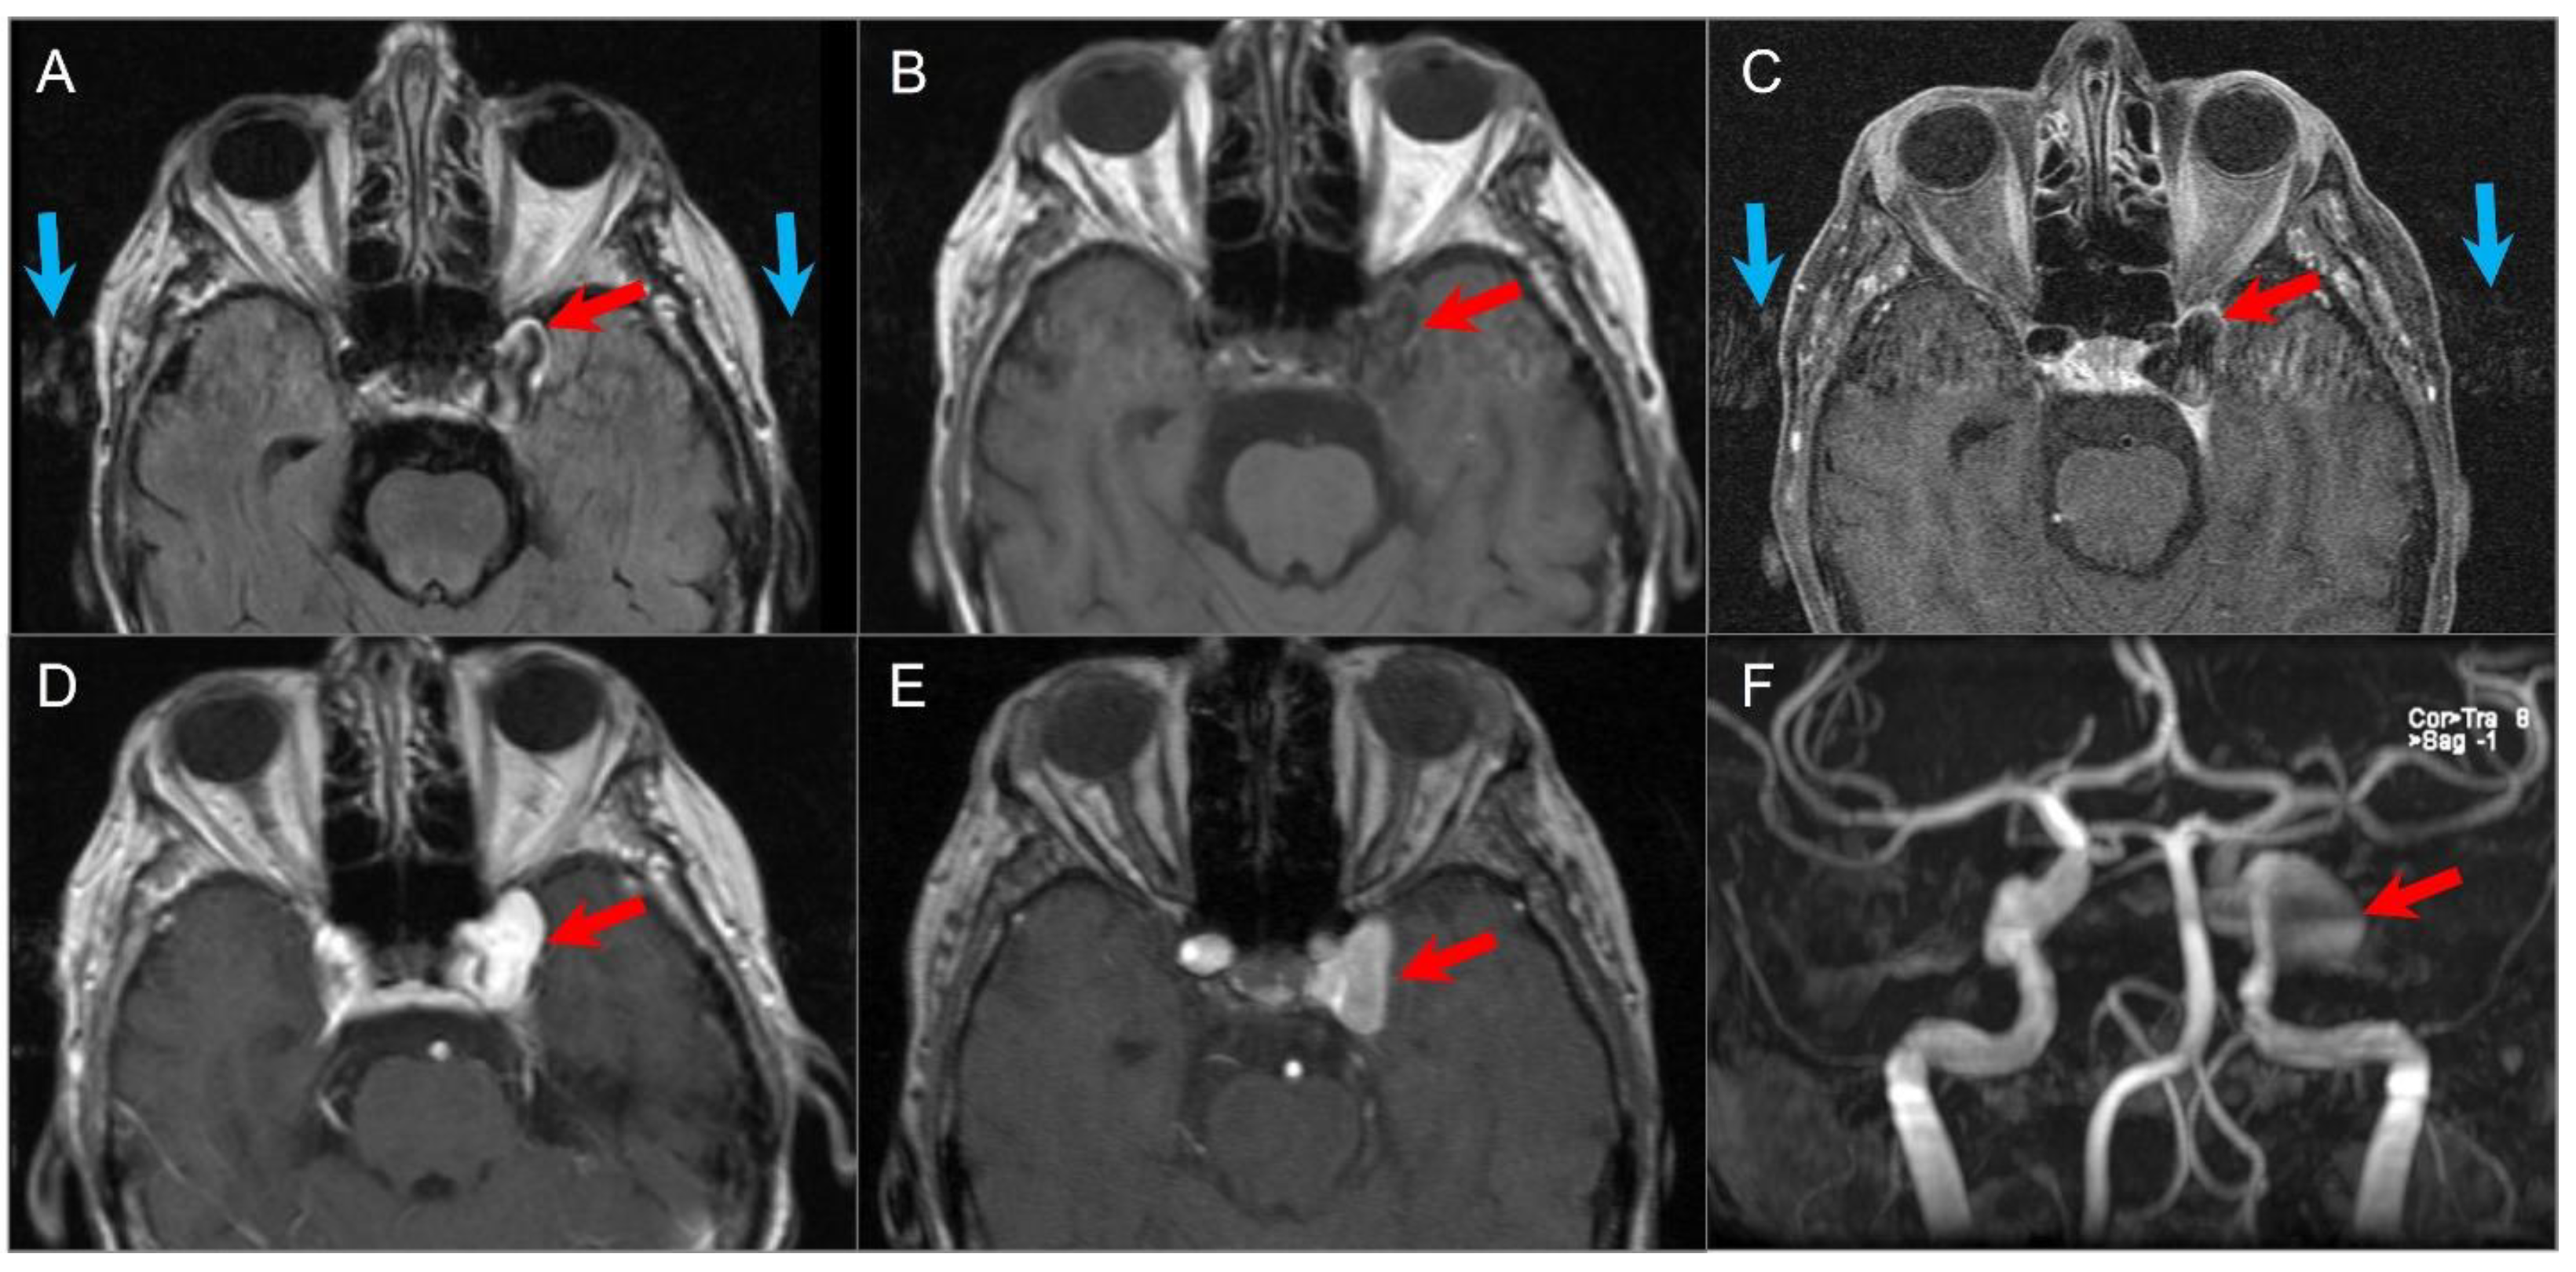

5.11. Giant Aneurysm